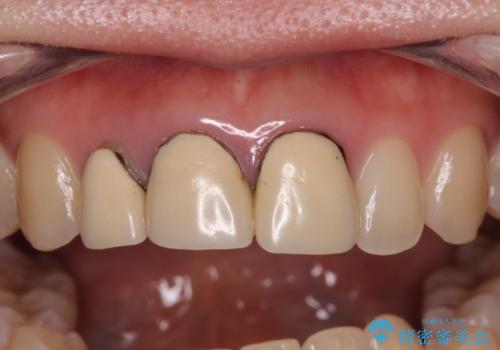

前歯の黒い縁を綺麗にしたい 前歯のオールセラミック

- 以前に装着した前歯のクラウンの縁が見えていることを気にして来院された患者様です。

根尖部に病変のある2歯は事前に根管治療を行い、オールセラミッククラウンにて補綴することとしました。